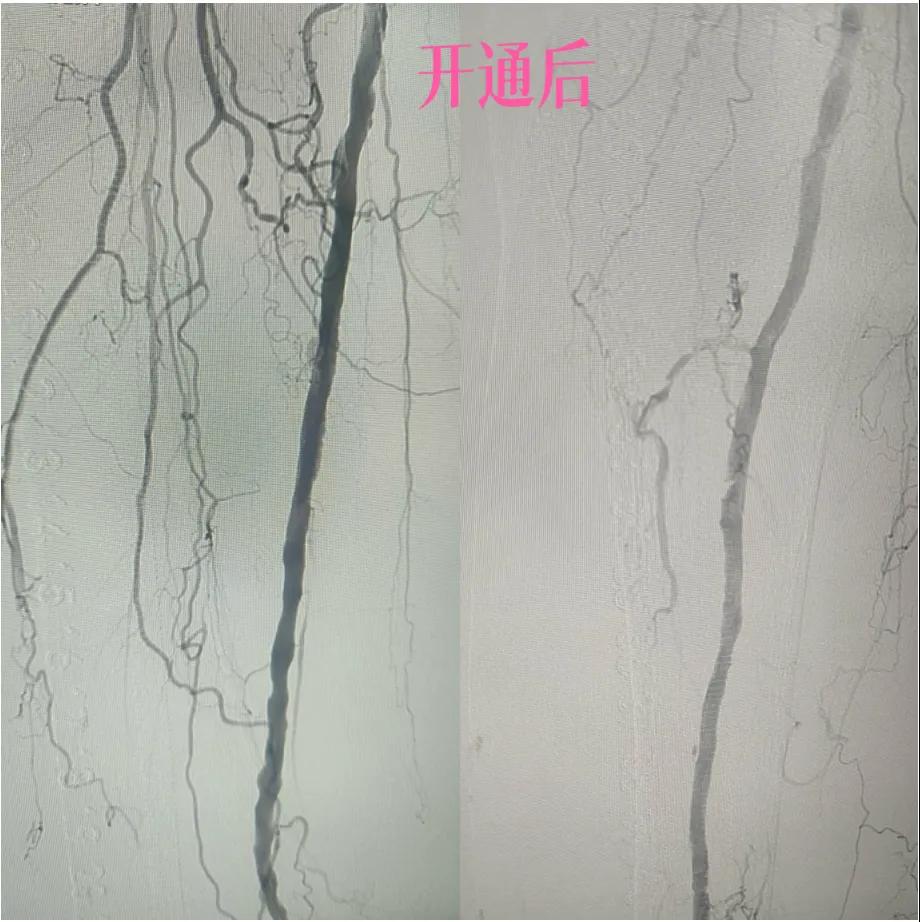

為了挽救患者的患肢,避免截肢,外二科血管外科介入團(tuán)隊(duì)經(jīng)過(guò)縝密的術(shù)前討論和評(píng)估,決定采用目前微創(chuàng)介入技術(shù)——下肢動(dòng)脈藥涂球囊擴(kuò)張成形術(shù)(DCB)。

3.  “球囊發(fā)力”:到達(dá)目標(biāo)閉塞段后,將未充氣的球囊導(dǎo)管送至病變部位。隨后,精準(zhǔn)控制壓力,使球囊緩慢充盈擴(kuò)張,如同在血管內(nèi)部進(jìn)行精細(xì)的“拓荒”,將堵塞的斑塊擠壓、塑形,撐開(kāi)狹窄的血管腔。

4.  即刻“見(jiàn)證”:再次造影顯示,原本狹窄閉塞的血管段血流恢復(fù)通暢!足部遠(yuǎn)端血管顯影較前明顯改善。手術(shù)過(guò)程順利,患者靜息痛較前明顯改善。